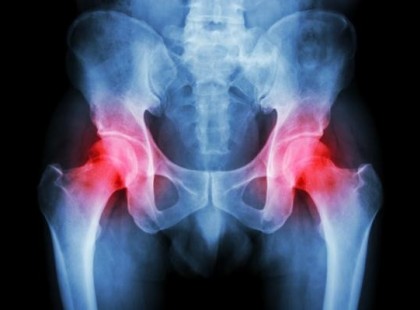

Így oldhatod ki gyorsan a húgysavat a testrészeidből, hogy megszűnjön a köszvény és az ízületi fájdalom.

A köszvény egy kóros állapot. Duzzanatot, merevséget és súlyos fájdalmat okoz, akár pár óra alatt. A fő oka a nagy...